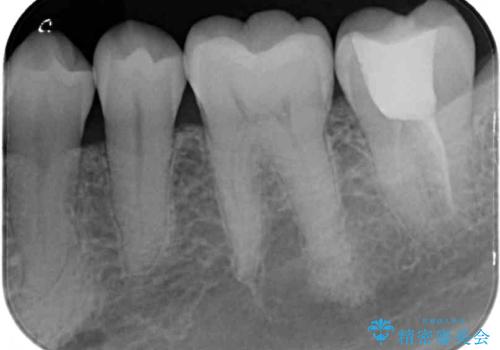

- 神経が取り除かれた歯が欠けてしまったとのことで来院された患者様です。

破折線が歯肉の中、深いところにまで及んでいる場合には歯周外科の適用となることを伝えた上で、補綴治療を行うこととしました。

破折部位を除去したところ、外科処置が必要な深さまで破折線が及んでいなかったため、速やかにジルコニアクラウンにて補綴を行うことになりました。

神経が取り除かれた歯、特に奥歯では、歯の破折が起こりやすいので、クラウンによる補綴治療が必要であることを実感した治療でした。